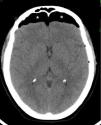

El hallazgo más frecuente quizás lo constituya la presencia de pequeñas imágenes focales que se distribuyen en la sustancia blanca encefálica y se visualizan hiperintensas en la RM ponderada en T2 o FLAIR (fig. 1). Estas imágenes se observan en aproximadamente un 12-47% de los pacientes migrañosos, siendo incierto su origen y significado clínico3. La importancia de este hallazgo radica en la posible confusión que puede generar con otras etiologías, como la esclerosis múltiple y los fenómenos microangiopáticos.